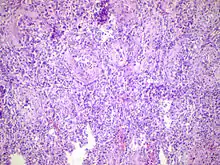

Acute epididymitis with abundant fibrinopurulent exudate in the tubules.

Histopathology image of inflamed epididymis and testis

Epididymitis can be classified as acute, subacute, and chronic, depending on the duration of symptoms.[2]